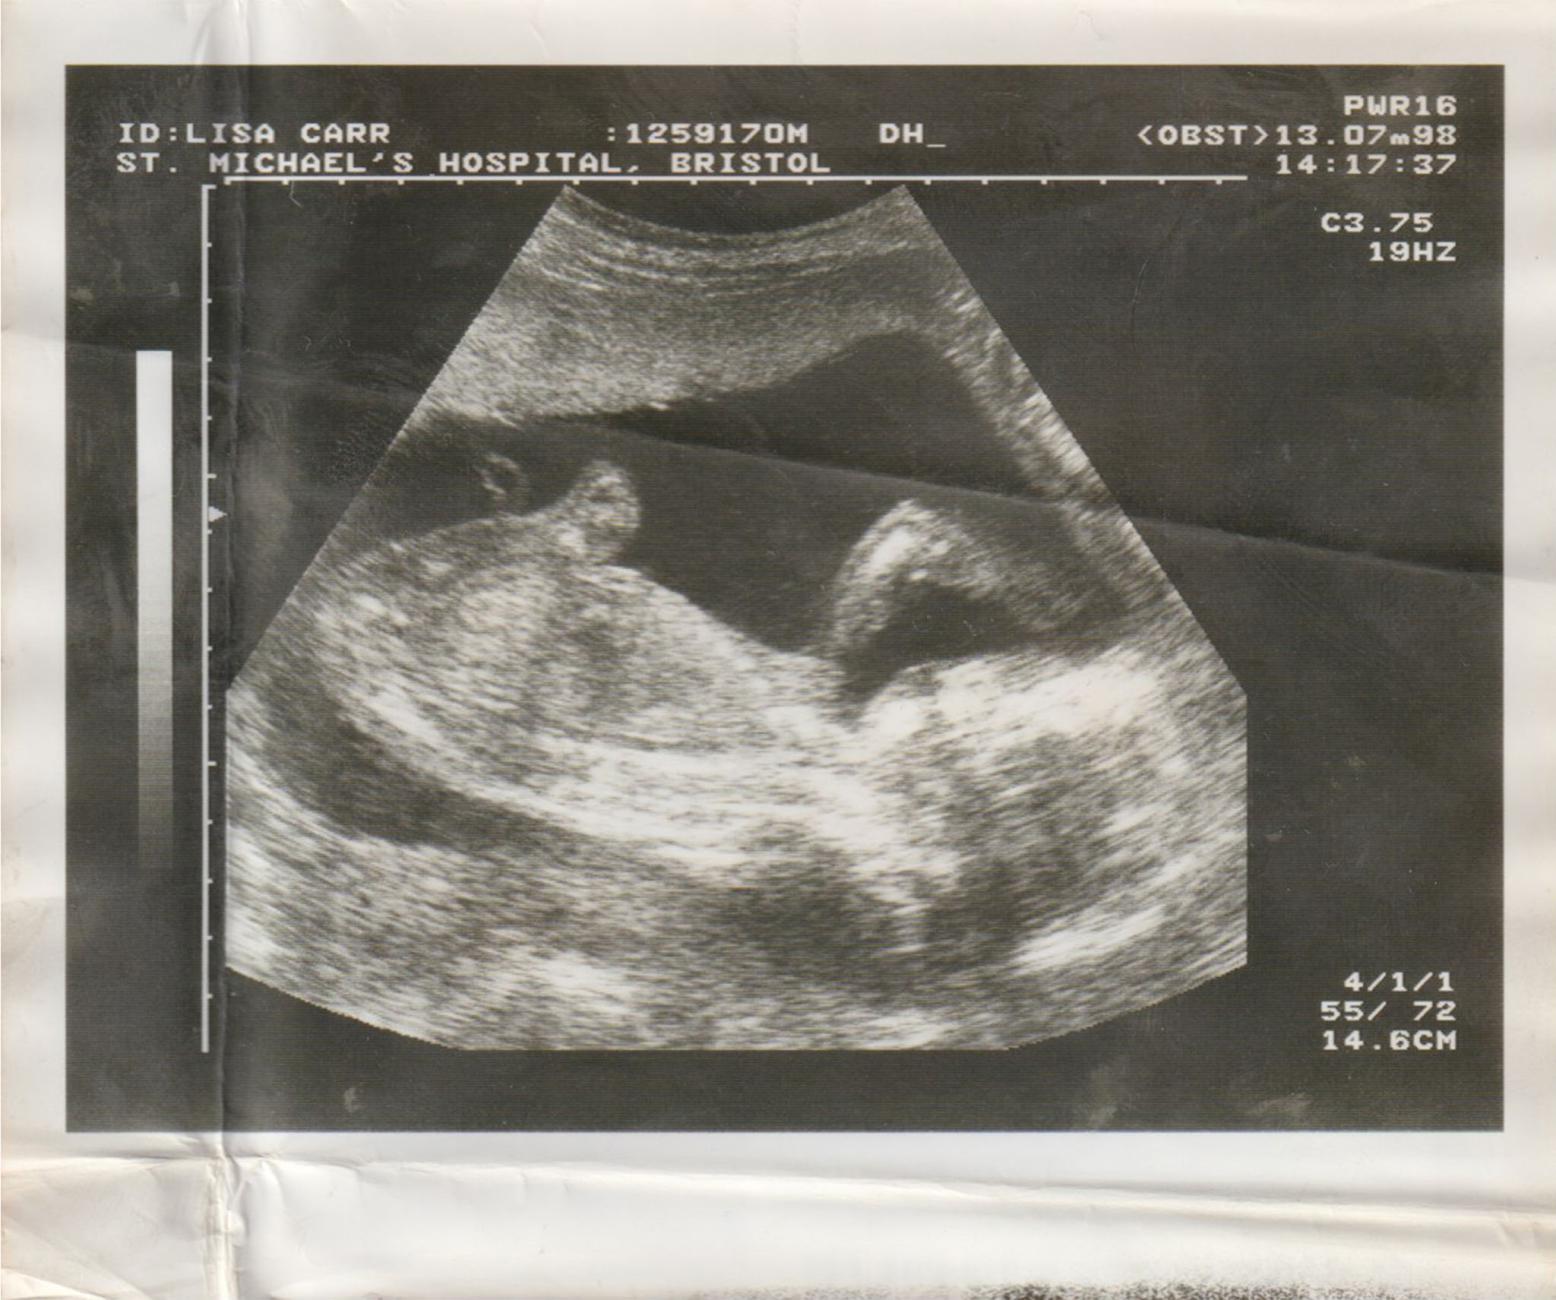

JCD: I would say out of all the completed projects that I have done in the past, my current project has been the most unfamiliar. Despite not being pregnant anymore and being nearly 2 years into my motherhood journey these experiences have been my most challenging experiences to date. From building up the courage to step in front of the camera to understanding my own boundaries and physical limitations when deciding to photograph myself, my son, and my partner.

I think my most defining challenge and milestone would have to be deciding to continue studying whilst pregnant and then whilst caring for a newborn. It was very difficult at times, and there were a lot of ups and downs, but I wouldn’t change anything.

I now create this work so that other women who hold the same or similar experiences to mine during pregancy, childbirth and becoming a mother. Can look to my project and see themselves represented in my images. For conversations around society's view of what a Mother should look like and just how unrealistic they are. Taboo conversations around unexpected pregnancy, loss, mental health, Black maternal health, the importance of representation, the negatives and positives of breastfeeding and the harsh realities of what becoming a parent means.

JCD: One of the many challenges was understanding a healthy balance between my personal life and my photographic practice. I had to learn how to balance being a photographer and a Mother and understanding when it’s appropriate to merge the two. And when it was time to put down my camera and step away from the project to allow myself time to rest and experience my pregnancy and early motherhood first-hand.